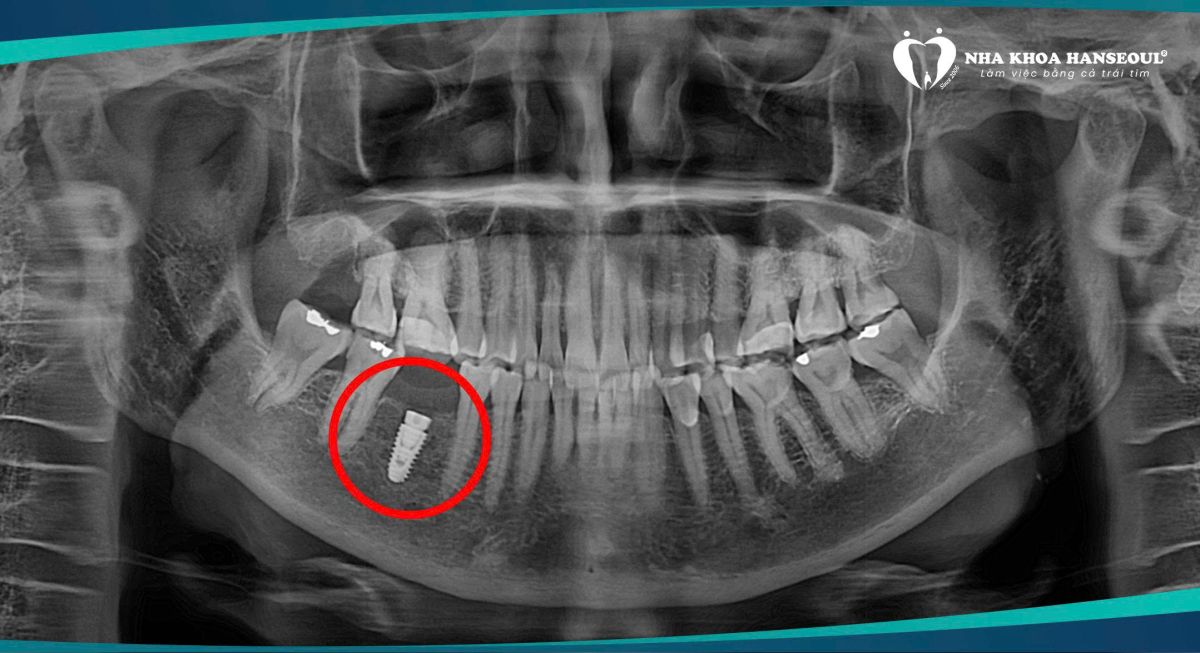

Cô được kiểm tra toàn diện bằng hệ thống chẩn đoán hiện đại. Bác sĩ phân tích phim rõ ràng, giải thích từng bước và trấn an tâm lý cho cô trước khi điều trị.3.2 Cấy Implant nhẹ nhàng

Khi thực hiện cấy trụ, cô Huệ bất ngờ vì không đau nhiều như mình từng lo sợ.Cô chia sẻ: “Cô sợ đau lắm, nhưng bác sĩ làm nhẹ nhàng lắm. Nhanh nữa, không đáng sợ như mình nghĩ.”

Nhờ công nghệ và tay nghề bác sĩ giàu kinh nghiệm, quy trình diễn ra êm ái, hạn chế xâm lấn và giúp cô hoàn toàn yên tâm.